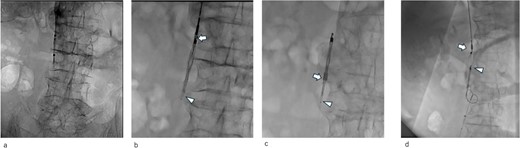

After confirming the absence of progressive anemia because of the hemorrhage from the femoral fracture, heparin was administered systemically. Following improved arterial blood oxygenation, NPPV was discontinued on hospital Day 3, and oxygen administration was discontinued on hospital Day 10. The patient was discharged on Day 15 of hospitalization. Enhanced computed tomography revealed that the IVCF did not move (Fig. 4a–c) and the pulmonary embolism improved; however, the thrombus remained in the left femoral and popliteal veins.

Computed tomography images 14 days after surgery. (a,b) The IVCF is still folded and not open. (c) Legs of IVCF are still folded.

IVCF is generally considered safe, with a low incidence of acute complications. In addition, instances of IVCF opening failure are very rare. Ganesh et al. reported that IVCF ‘failed to open’ only in 27 (0.18%) out of 14 784 cases [2]. The etiology of IVCF opening failure has been attributed to entanglement of the IVCF legs [3], misplacement into the gonadal or femoral veins [3, 4], or thrombus formation in the delivery sheath during deployment [5, 6]. In our case, the etiology was assumed to be entanglement of the IVCF legs or misplacement of the IVCF tip into the left gonadal vein based on the shape of the failed ICVF (Figs 2a and 4c).

Despite being effective in avoiding the migration of the unopened IVCF and treatment of the acute pulmonary thromboembolism, our approach remained of concern. IVCFs have been reported to cause chronic perforation to the IVC wall, even with appropriate deployment [9]. In this patient, the tip of the unopened IVCF was folded (Figs 3 and 4c); thus, the risk of perforation increased because of the stiffness of the folded IVCF legs. Therefore, close monitoring is required.